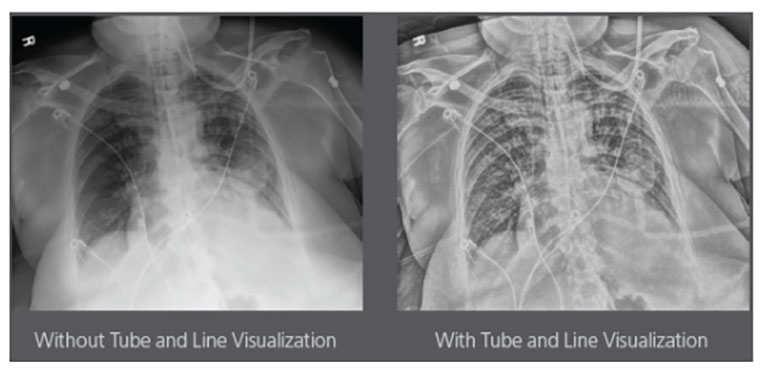

Carestream Introduces New Software Update to Boost Diagnostic Accuracy

Carestream today announced the latest update to its Image Suite V4 Software, MR 11: a series of enhancements to help improve customer confidence and increase diagnostic accuracy [...]

By Praveen Rajgopal, Global Product Marketing Manager

CARESTREAM Image Suite V4 MR11 has set a new standard for workflow efficiency, offering a robust set of features and functionalities to enhance clinical confidence in healthcare professionals. Using an auto-generated companion image from a single exposure, leverage a range of image processing options to increase diagnostic accuracy and enhance patient care.